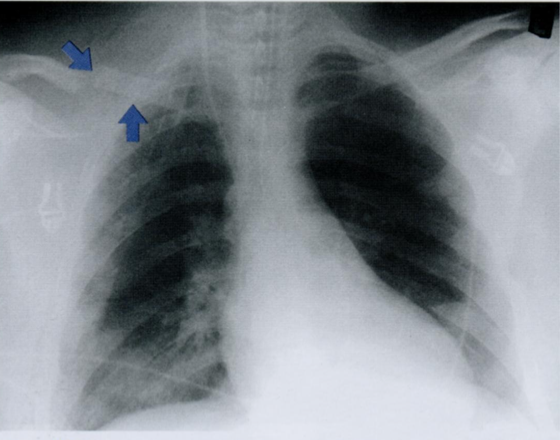

Как вы оцените объект, отмеченный стрелкой?

Это очередной источник недоразумения, который может быть интрепертирован, как внутрилегочное образование. Этот соски.

В некоторых случаях после пометки сосков накожными металлическими маркерами выполняется контрольная рентгенограмма (фото ниже).